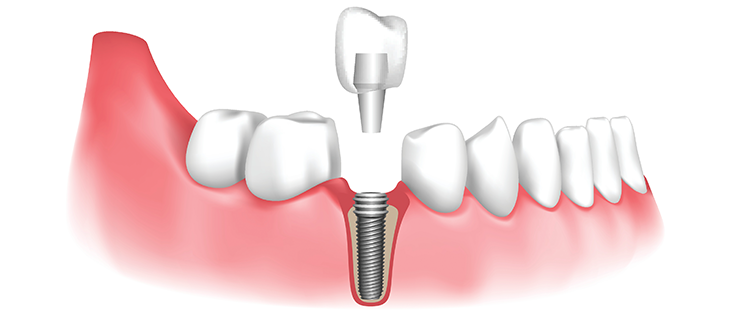

🩺 ما هي زراعة الأسنان؟

زراعة الأسنان هي إجراء طبي

يتم فيه تثبيت جذر صناعي (غالبًا من التيتانيوم) داخل عظم الفك،

ثم يتم تركيب تاج (سن صناعي) فوقه.